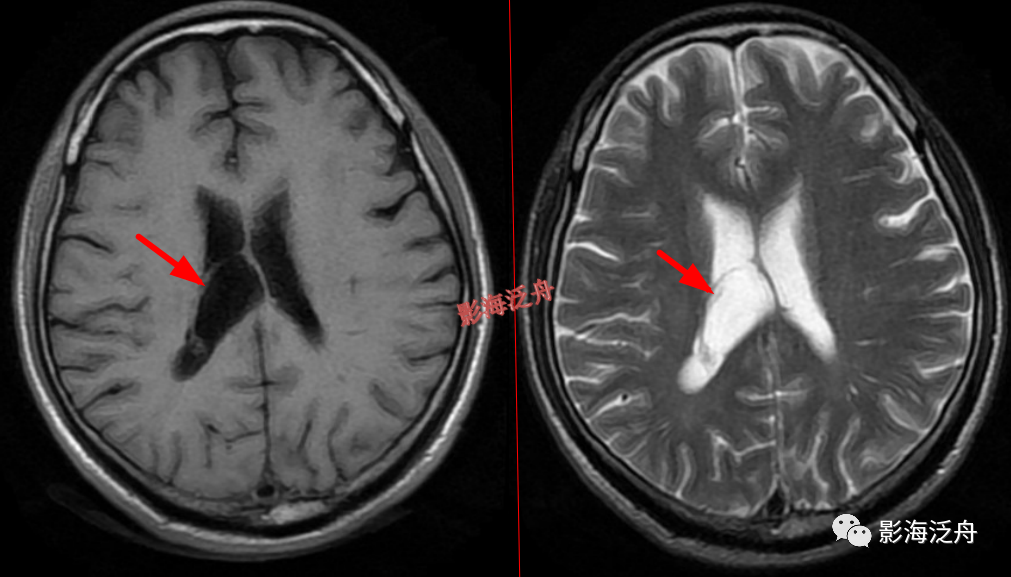

右侧侧脑室体部囊性占位(红箭),整体信号与脑脊液一致,病灶边缘部分显示,透明隔稍移位。

灰质移位,患者既往有癫痫

病史。右侧侧脑室前角及左侧侧脑室后角可见异位的灰质结节(红箭),与大脑皮层下的灰质信号一致(绿箭),灰质异位患者多伴有癫痫症状。

透明隔缺如,我自己漏诊过的病例。上面有很多正常的图像可供对比观察。